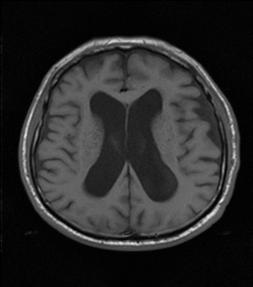

03. HIDROCEFALIA NORMOTENSIVA

Definición

Aumento en el tamaño de los ventrículos como resultado de la acumulación excesiva de líquido cefalorraquídeo (LCR), pero con presión intracraneana en rango normal.

Diagnóstico

Resonancia magnética (prueba inicial), tomografía computarizada

Ventriculomegalia sin agrandamiento del surco

Hipodensidad periventricular debido a edema periventricular